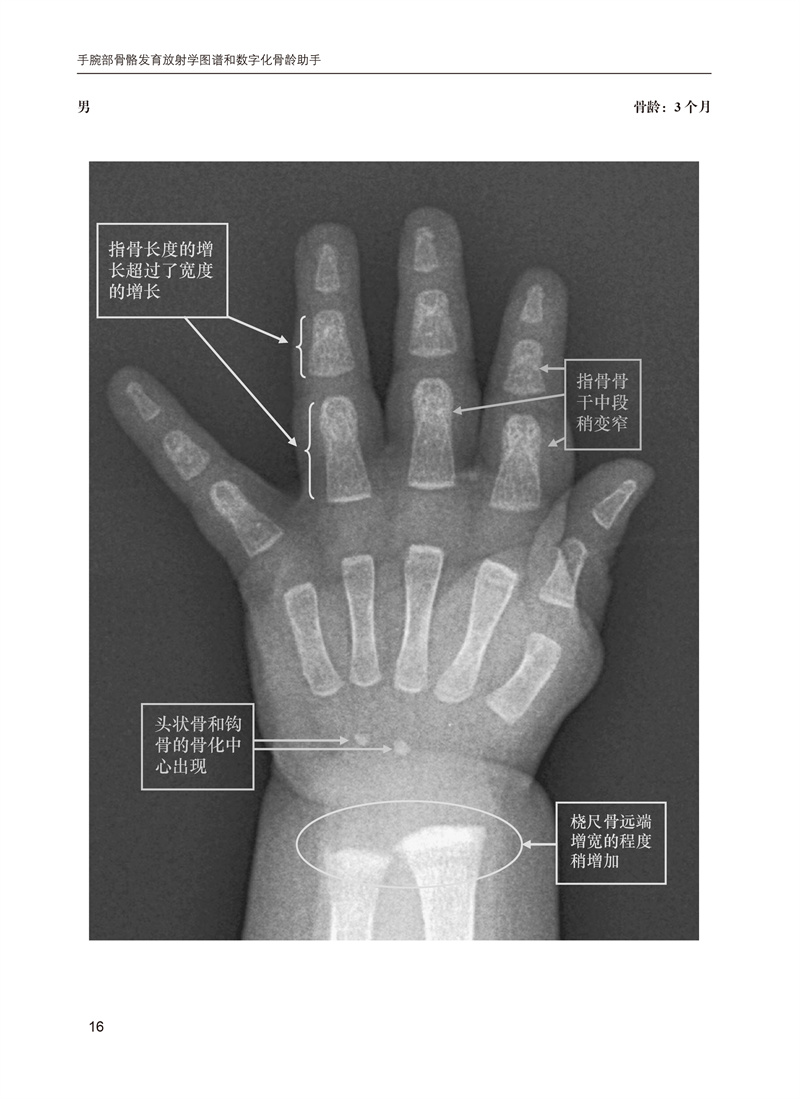

骨龄是国际公认的准确反应儿童生长发育的重要指标,也是临床医学、体育及法医学领域不可或缺的一项重要检查。本书基于广受欢迎的Greulich和Pyle图谱,将儿童骨骼成熟度的确定方法现代化。它提供了大量的图像,这些图像是从弗吉尼亚大学的PACS中的数千张数字X光片中精心挑选出来的,以最佳展示重要发育性骨特征,并按年龄和性别组织,以便快速参考。为了便于学习和临床图像分析,带注释和不带注释的图像成对出现,以便容易比较。图像上的简洁注释取代了冗长的文本,以提供更快速、更清晰的骨骼年龄标志。这些注释强调了重要而微妙的特征,帮助区分否则看起来相似的图像。本书分为两大部分:男性和女性各年龄段标准图谱。本书是一个高质量的左手腕X线片标准图谱,捕捉了Greulich和Pyle公认标准的重大和细微细节。鉴于骨龄应用的广泛性,手和腕部骨骼发育不仅旨在为实践和培训放射科医生提供参考,也适用于所有将骨龄研究作为实践一部分的人员。